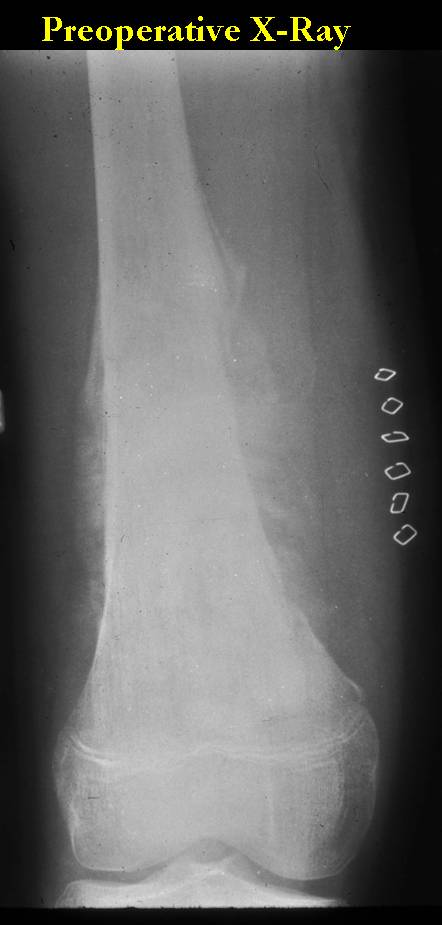

These are examples of the gross pathology specimens of resected conventional osteosarcoma, consisting of both bony and soft tissue areas. X-rays of the specimens are included.

- Osteosarcomas are composed of ossified or non-ossified tissue

- Ossified tissue is yellow-white and hard

- Less ossified tissue is soft and less yellow

- Non-ossified tissue is tan and fleshy

- Most (95%) of conventional osteosarcomas penetrate the cortex and form a large extraosseous soft tissue mass

- The lesion permeates the marrow spaces

- Osteosarcomas usually infiltrate the marrow several centimeters away from the main tumor mass

- Skip lesions may be apparent that are separated from the main tumor by normal marrow

- Osteosarcomas may also have cartilaginous components that appear as translucent lobules, and/or fibrous components that are tan, soft to firm rubbery areas

- Osteoblastic areas are usually white to yellow, firm, hard and gritty

- The consistency of the tumor depends on the amount of osteoid deposition, cartilaginous and fibrous areas

- Foci of hemorrhage and necrosis are common

- Periosteal reactions such as the Codman’s triangle are apparent at periphery of soft tissue mass

- Osteosarcomas rarely penetrate the growth plate grossly

- Invasion of the joint is uncommon but can occur by cortical penetration, joint capsule extension, or extension along cruciate ligaments